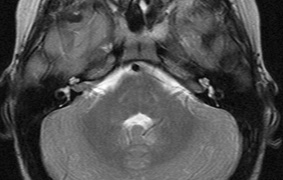

STURGE-WEBER SYNDROME Sturge (1879) reported the case of a child with facial “port-wine stain,” epilepsy, buphthalmos, and a dark choroid.204 Schirmer had noted the association of the facial vascular malformation and glaucoma in 1860.3 Weber (1922) reported brain X-ray findings of parallel streaks (“railtrack” sign), which he interpreted to represent calcific changes (Fig. 19).205

The PWS may not entirely respect the midline, possibly a reflection of transmedian innervation.212 The lesion grows proportionally with the child, often becoming darker in color. 213 The overlying skin may develop nodularity or hypertrophy in two-thirds of patients (by the fifth decade).214 Treatment with a pulsed-dye laser may significantly improve the appearance, but recurrence (i.e., redarkening) is possible.215,216 A deficit in the number of perivascular nerves in port-wine stains suggests that abnormal neural modulation of vascular flow may be involved in their pathogenesis.217 Intracranial leptomeningeal capillary vascular malformation (Figs. 21 and 22) is associated with seizures and contralateral neuromuscular weakness. Central nervous system involvement correlates highly with ipsilateral involvement of the V1 dermatome by a PWS.208,218